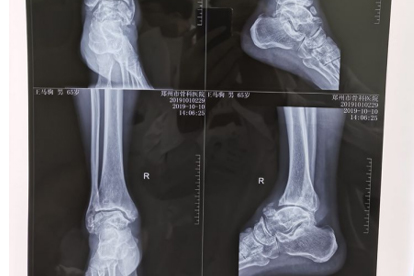

踝关节内翻扭伤易造成距腓前韧带或跟腓韧带部分撕裂,按压外踝前下方时疼痛明显,可能伴随肿胀淤青。轻度损伤需弹性绷带固定2-3周,中重度损伤需支具保护,可配合使用消痛贴膏、雪山金罗汉止痛涂膜剂等促进修复。

先天性腓骨肌沟浅或外伤后肌腱支持带断裂,会导致肌腱滑脱产生弹响痛。动态超声检查可确诊,反复发作者需手术重建肌腱鞘管,术后需穿戴步行靴4-6周。